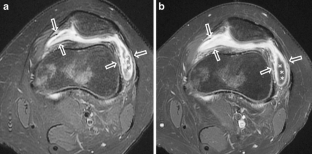

MR findings of synovial disease in children and young adults: Part 1

Synovial diseases in children can be classified into normal structures as potential sources of pathology (synovial folds: plicae, infrapatellar fat pad clefts); noninfectious synovial proliferation (juvenile idiopathic arthritis, hemophilic arthropathy, lipoma arborescens, synovial osteochondromatosis, pigmented villonodular synovitis, reactive synovitis), and infectious synovial proliferation, deposition disease, vascular malformations, malignancy (including metastasis) and intra-articular/periarticular cysts and cyst-like structures (ganglia). Familiarity with characteristic MR imaging findings of synovial diseases in children and young adults will enable a more confident diagnosis for earlier intervention and directed therapy. The first part of this paper will cover potential pathology of normal synovial structures as well as noninfectious synovial proliferation.